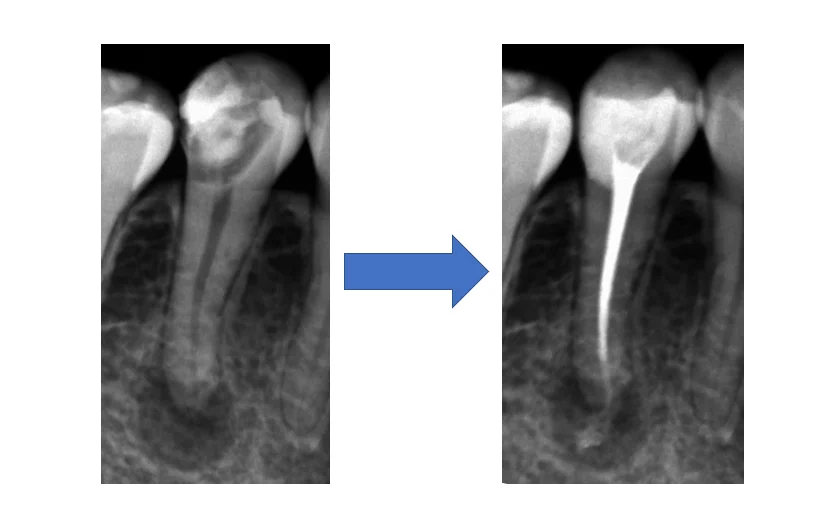

で、こちらが術後(根管充填後)のレントゲンです。

歯の周りにコンポジットレジンで隔壁を作成していますが、歯との間に段差が無いのが分かるかと思います。(紫の丸の所)

根の先までお薬がしっかりと綺麗に詰まっています。(赤い丸の所)

(根の先から飛び出している材料はシーラーという接着剤ですが、少量であれば吸収されるので問題が無いと言われています。)

術前術後の比較です

根の先の膿のサイズに劇的な変化はありません。

というのも、この治療の開始から終了までが1ヵ月半という短さの為です。

根の先に元通り骨が出来上がってくるまでには半年から数年の期間が掛かってしまいます。

ですので、ほんとうに治ったかどうかはそれだけの期間が開いてからじゃないと分からないのです・・・。